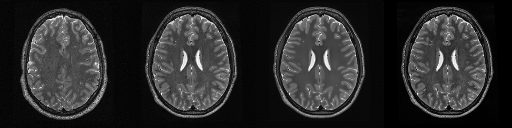

HCP T2w dataset

We utilize images from the publicly available Human Connectome Project (HCP) [51] T2-weighted (T2w) images dataset for the task of compressed sensing, which contains brain images from 47 patients. The HCP dataset includes cross-sectional images of the brain taken at different levels and angles.

Compressed sensing

We train a flow-based model from scratch on 10,000 randomly sampled images, utilizing the ncsnpp architecture [9] with minor adaptations for grayscale images. We employ compression rates , meaning . The measurement operator is given by a subsampled Fourier matrix, whose sign patterns are randomly selected. We evaluate our reconstruction algorithm’s performance on 200 randomly sampled test images.

We present the quantitative and qualitative results of compressed sensing in Tab. 1 and Fig. 4, respectively. As shown in Tab. 1, our method consistently achieves the best performance across varying compression rates . In Fig. 4, our method produces reconstructions that are more faithful to the original images, with fewer artifacts, leading to higher accuracy and clearer details.